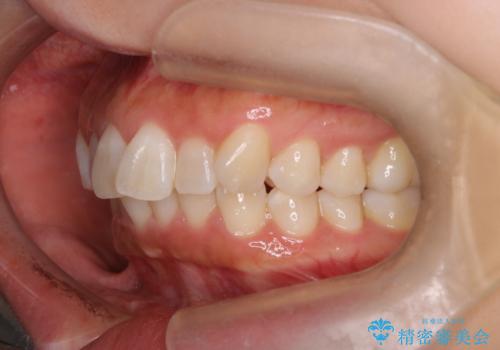

- 上下前歯のがたつきを主訴に来院されました。

口元も下げたいということもあり、上2本抜歯を行い治療を行いました。

抜歯を行い、前歯のがたつき、前歯の出ているところを改善できました。